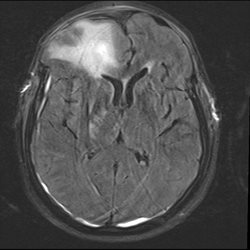

37yo female who fell out of a moving vehicle presenting with altered mental status and confused at scene. CT and MR